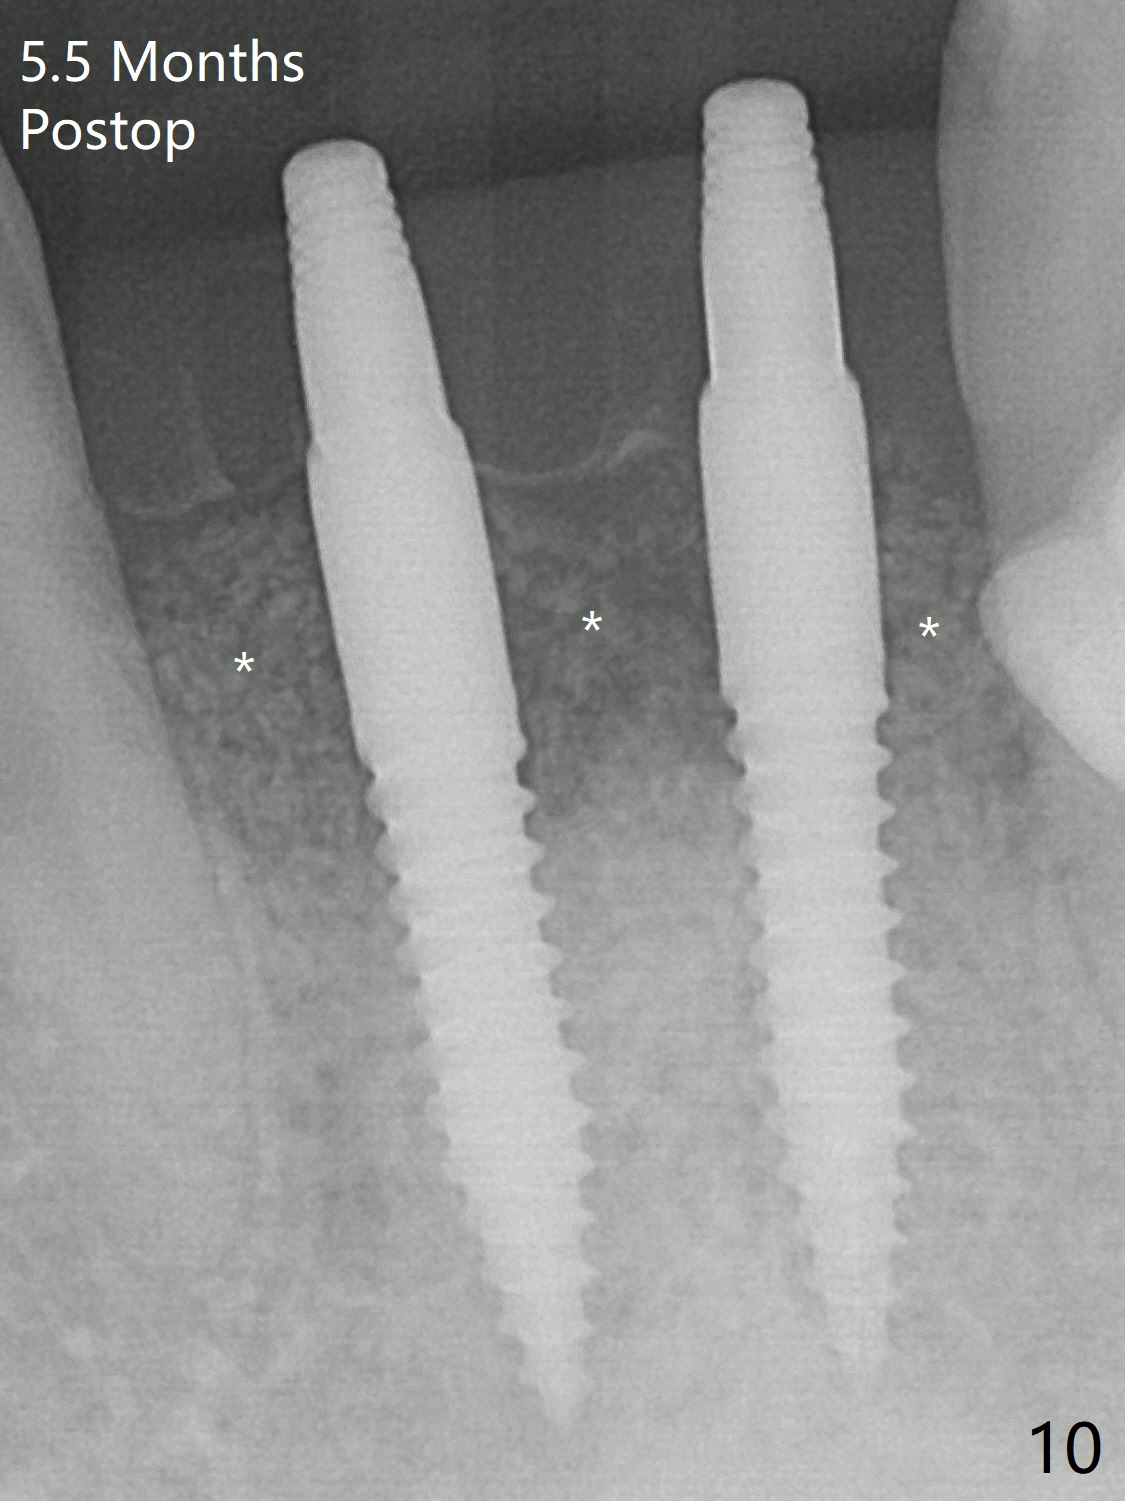

When dummy implants are placed partially, there is a large bony defect (Fig.4 *). After final implants (3x14(4) mm) are placed, allograft is placed coronally (Fig.5 *). Hard tissue heals 5.5 months postop (Fig.10 with formation of apparent bony trabeculae: *).